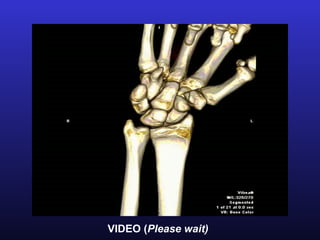

VIDEO (Please wait)

Midcarpal rotation          VIDEO (Please wait)

VIDEO

(Please wait)

VIDEO (Please wait) Anterior midcarpal clunking